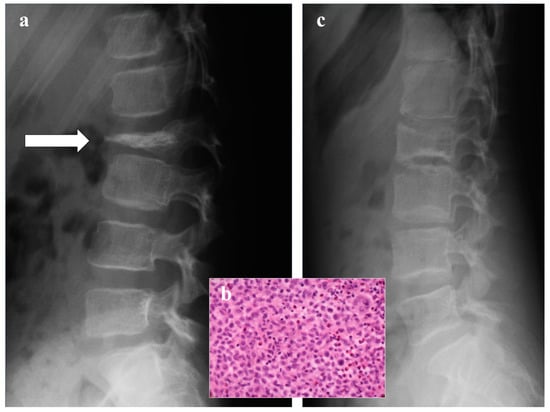

Langerhans Cell Histiocytosis

- Nesbit, M.E.; Kieffer, S.; D’Angio, G.J. Reconstitution of vertebral height in histiocytosis X: A long-term follow-up. J. Bone Joint. Surg. 1969, 51, 1360–1368. [Google Scholar] [CrossRef]